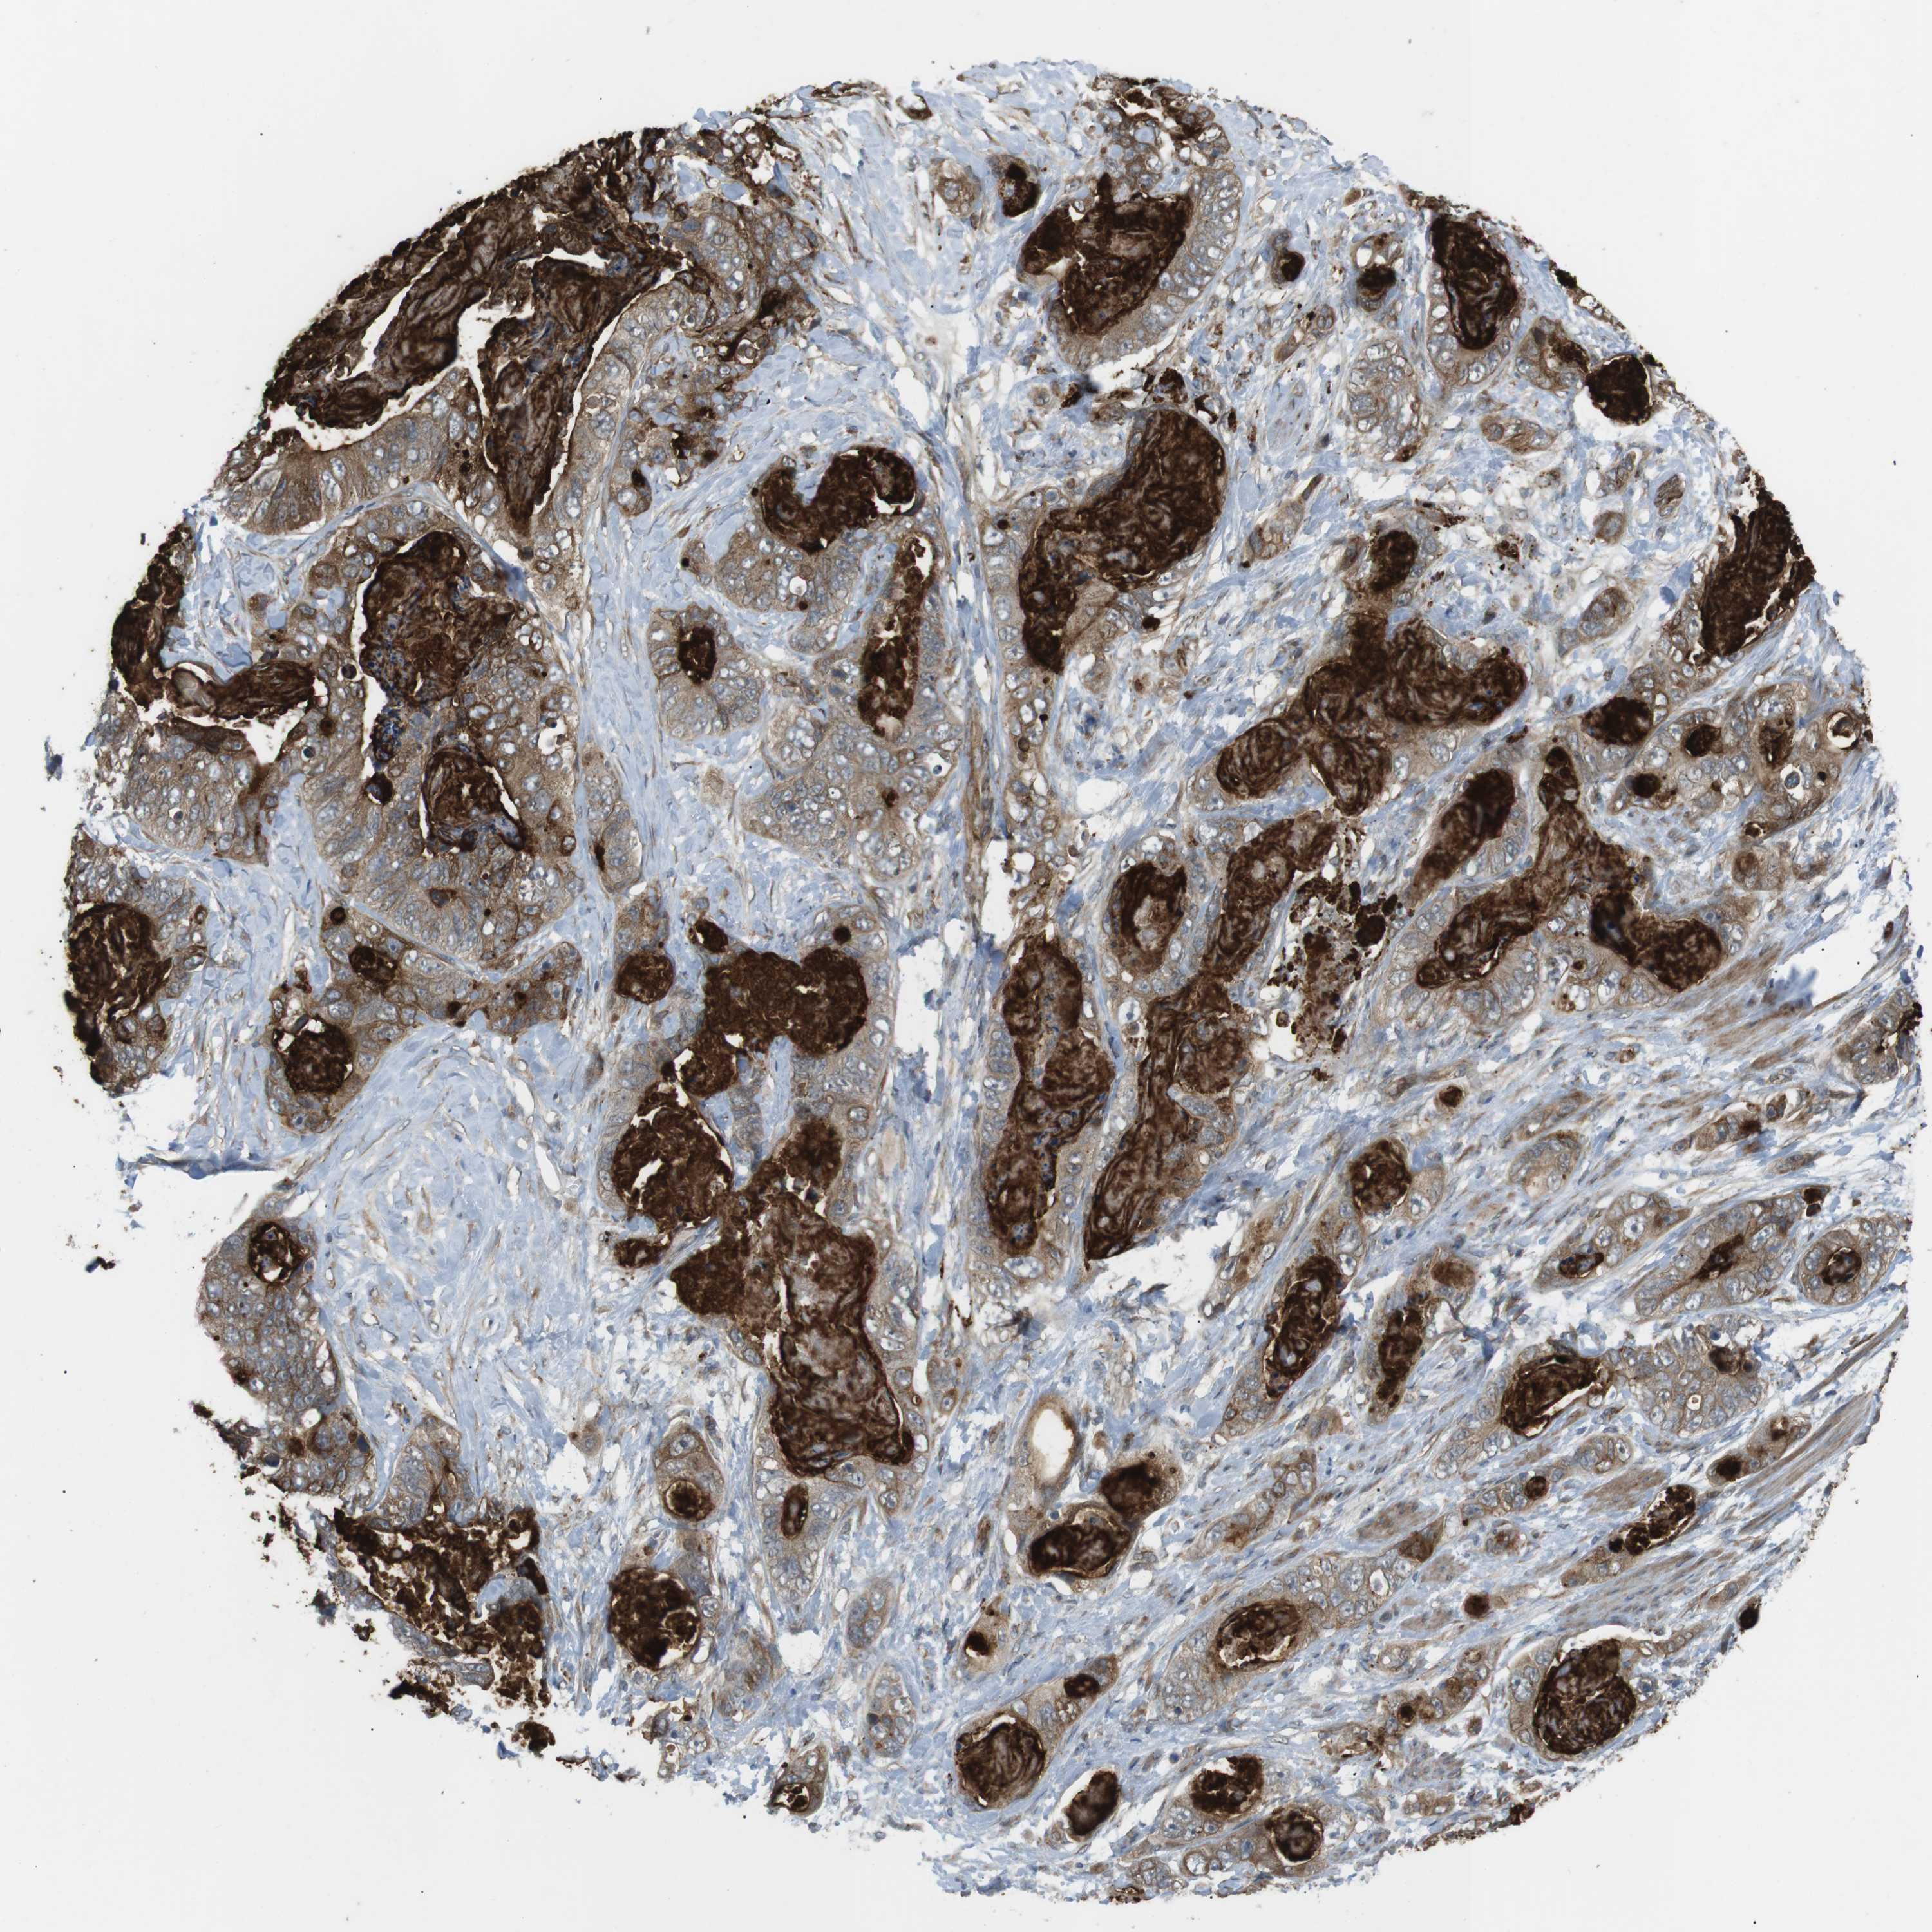

STOMACH CANCER - Protein expressioni

A mouse-over function shows sample information and annotation data. Click on an image to view it in a full screen mode. Samples can be filtered based on level of antibody staining by selecting one or several of the following categories: high, medium, low and not detected. The assay and annotation is described here.

Note that samples used for immunohistochemistry by the Human Protein Atlas do not correspond to samples in the TCGA dataset.

Antibody stainingi

Antibody staining in the annotated cell types in the current human tissue is reported as not detected, low, medium, or high, based on conventional immunohistochemistry profiling in selected tissues. This score is based on the combination of the staining intensity and fraction of stained cells.

Each image is clickable and will lead to virtual microscopy that enables deeper exploration of all samples and also displays staining intensity scores, fraction scores and subcellular localization as well as patient and tissue information for each sample.

Antibody HPA015643

Staining

High

Medium

Low

Not detected

Intensity

Strong

Moderate

Weak

Negative

Quantity

>75%

75%-25%

<25%

None

Location

Nuclear

Cytoplasmic/membranous

Cytoplasmic/membranous,nuclear

Adenocarcinoma, NOS